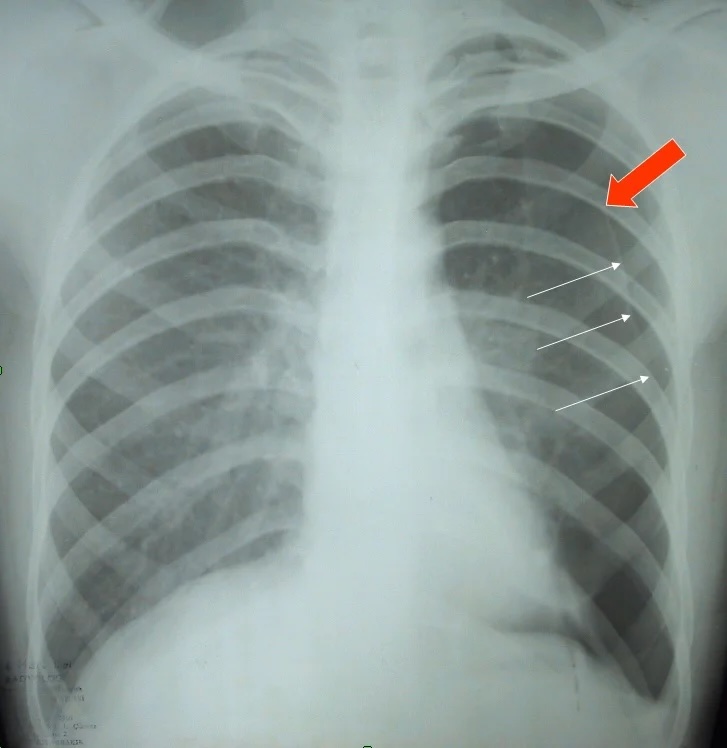

Основным методом визуализации является рентгенография органов грудной клетки. Обследование проводится в прямой и боковой проекциях грудной клетки в вертикальном положении пациента, при невозможности — в положении лежа, с дополнительной прицельной съёмкой подозрительного гемиторакса на вдохе и выдохе. Визуализируются исключительно прямые признаки: наличие газа в плевральной полости, отслоение лёгочной ткани и отсутствие сосудистого рисунка за пределами лёгочного края. Цель исследования — подтвердить наличие свободного воздуха в плевральной полости, определить объём, локализацию и возможные признаки напряжённого пневмоторакса.

Рентгенография выявляет следующие признаки пневмоторакса:

- Чёткая визуализация свободного плеврального газа в виде просветления без лёгочного рисунка между грудной стенкой и смещённым краем коллабированного лёгкого.

- Отчётливо ограниченный край лёгочной ткани, отступающий медиально от грудной стенки.

- Уменьшение объёма поражённого лёгкого с выраженным спадением его долей.

- Отсутствие лёгочного сосудистого рисунка в зоне пневмоторакса, особенно в верхнебоковых отделах.

- Смещение средостенных структур и купола диафрагмы при выраженном (напряжённом) пневмотораксе.

- Уровень газа и жидкости при одновременном наличии гидропневмоторакса, выявляемый как горизонтальная граница на фоне просветления.